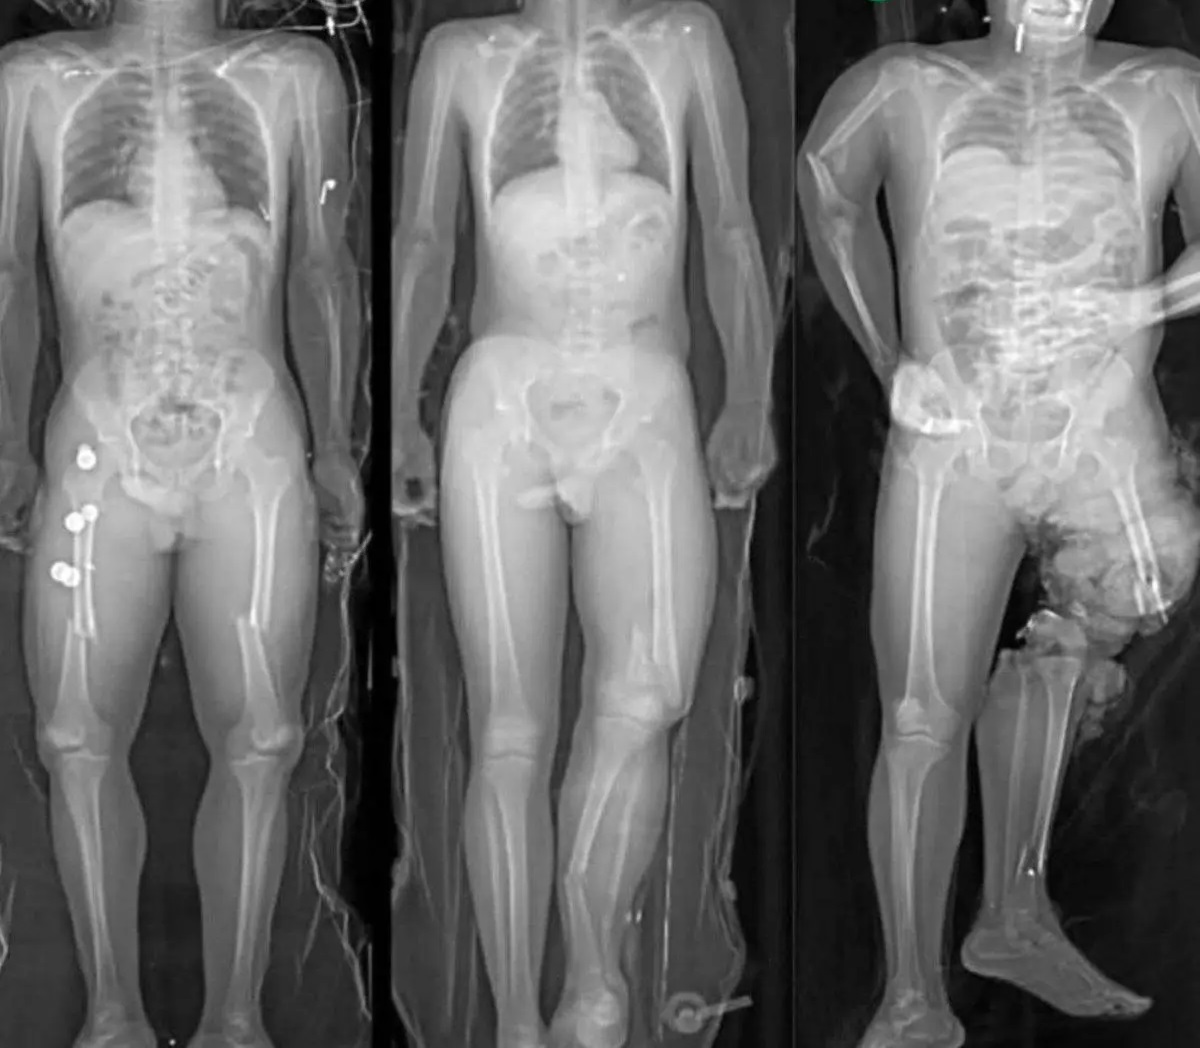

در یک تصادف جادهای، سه سرنشین بدون کمربند ایمنی آسیبهای شدیدی دیدند که تنها به دلیل نحوه نشستنشان متفاوت بود.

سمت چپ: پاها روی هم؛ بدن پیچخورده و شکستگیهای پیچیده در استخوانهای پا.

وسط: نشستن عادی؛ آسیب کمتر، اما همچنان جدی.

سمت راست: پا روی داشبورد؛ کیسه هوا پا را به لگن کوبید و استخوانهای لگن و ران خرد شد – آسیبی مادامالعمر.

همیشه کمربند ببندید، پا را روی داشبورد نگذارید و پاها را روی هم نیندازید.